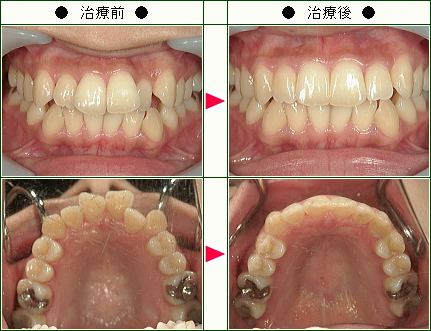

☆歯のデコボコ矯正症例(yayoi様 30歳 女性)